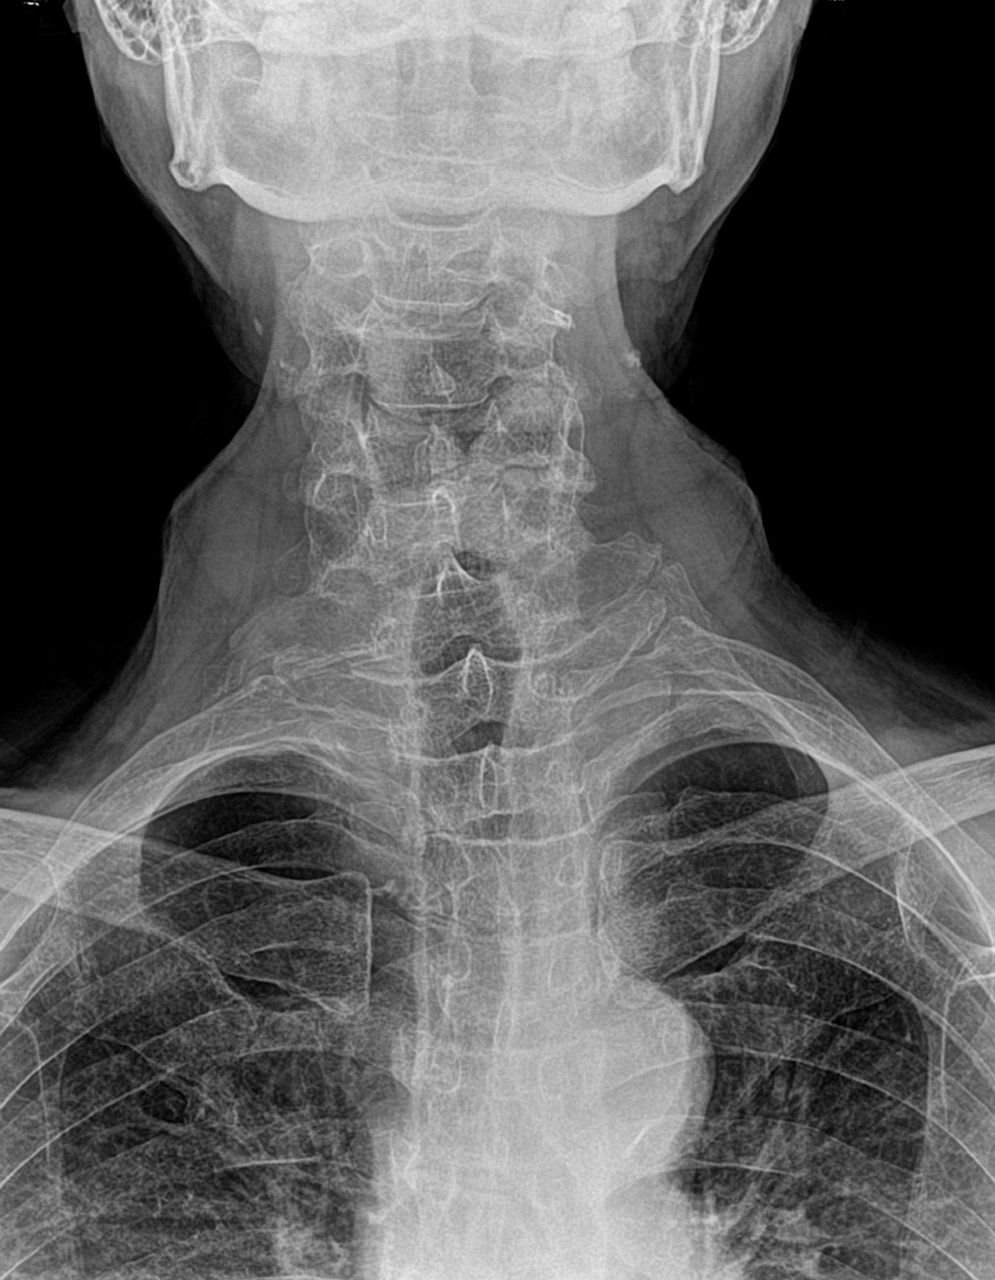

Been having neck, shoulder, arm and hand pain. Found a good Chiropractor X-ray revealed C5/C6 totally compressed. Also part of a vertebrae was broken off. Last year I was carrying a heavy item and backed into edge of a shelf, hurt like hell but did not think I broke something. As long as I can keep riding I'll be good.